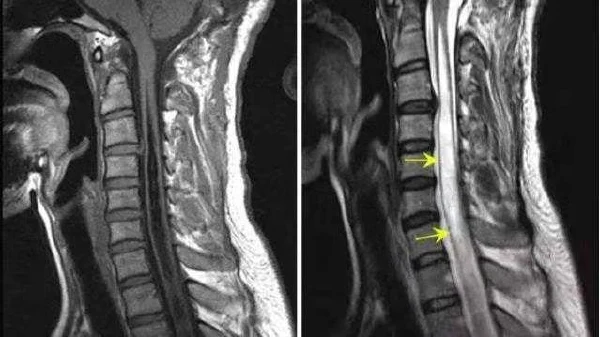

根据这名患者的病历资料,他在持续的左颈肩痛和左上肢无力后,经过头颈部MRI检查,最终被确诊为脊髓空洞症。该诊断表明患者需要接受进一步的治疗和护理。

脊髓空洞症的形成机制比较复杂,通常与脑脊液的循环障碍有关。脑脊液无法正常流动,因而积聚在脊髓内部,逐渐形成空洞。这种空洞会压迫周围的神经组织,导致一系列症状。例如,患者在近期持续感觉到左颈肩痛,并且伴有左上肢疼痛和无力,这些症状正是由于脊髓空洞对神经的压迫所致。